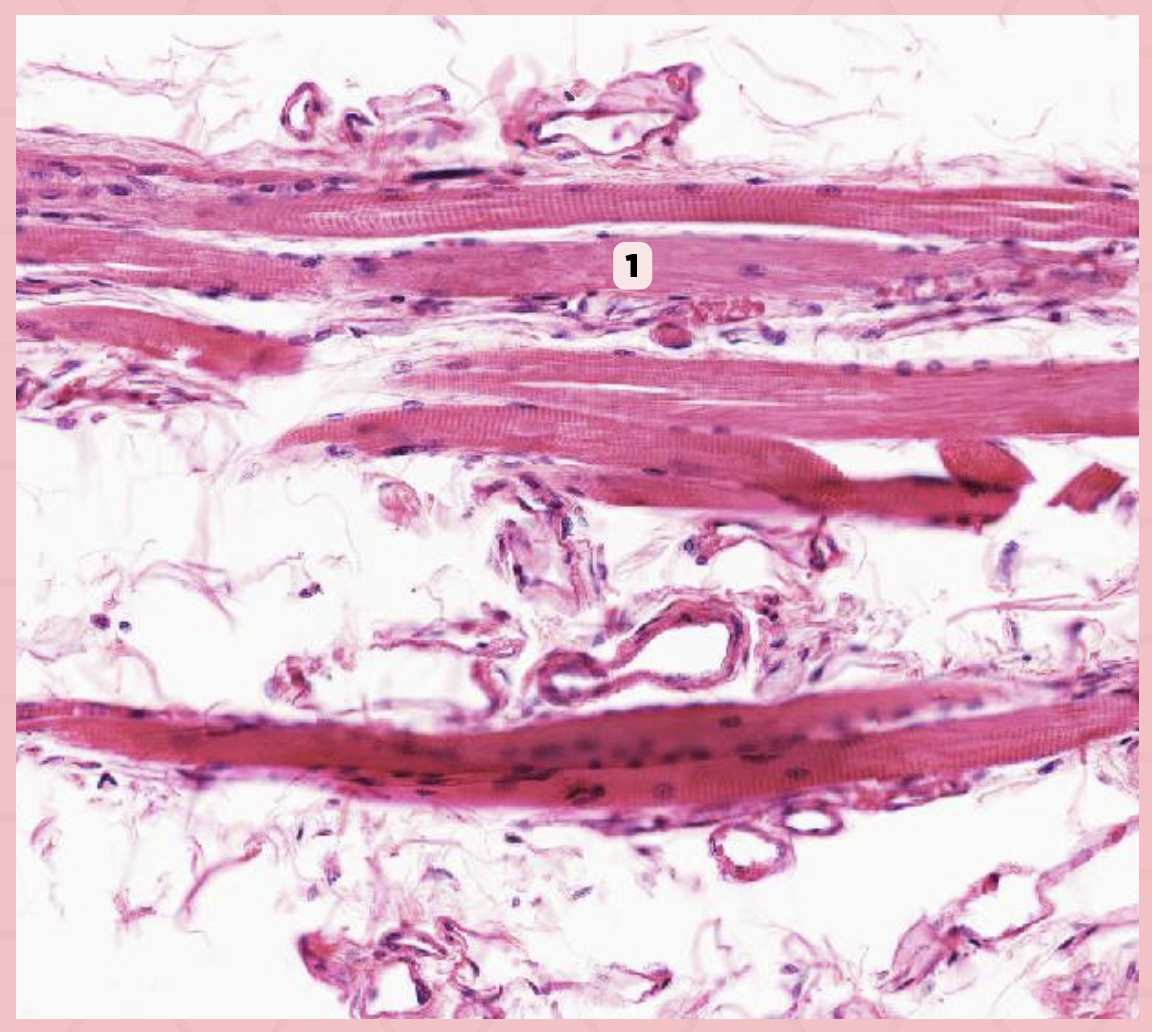

Skeletal Muscle Fibers

Identify the structure labeled as 1.